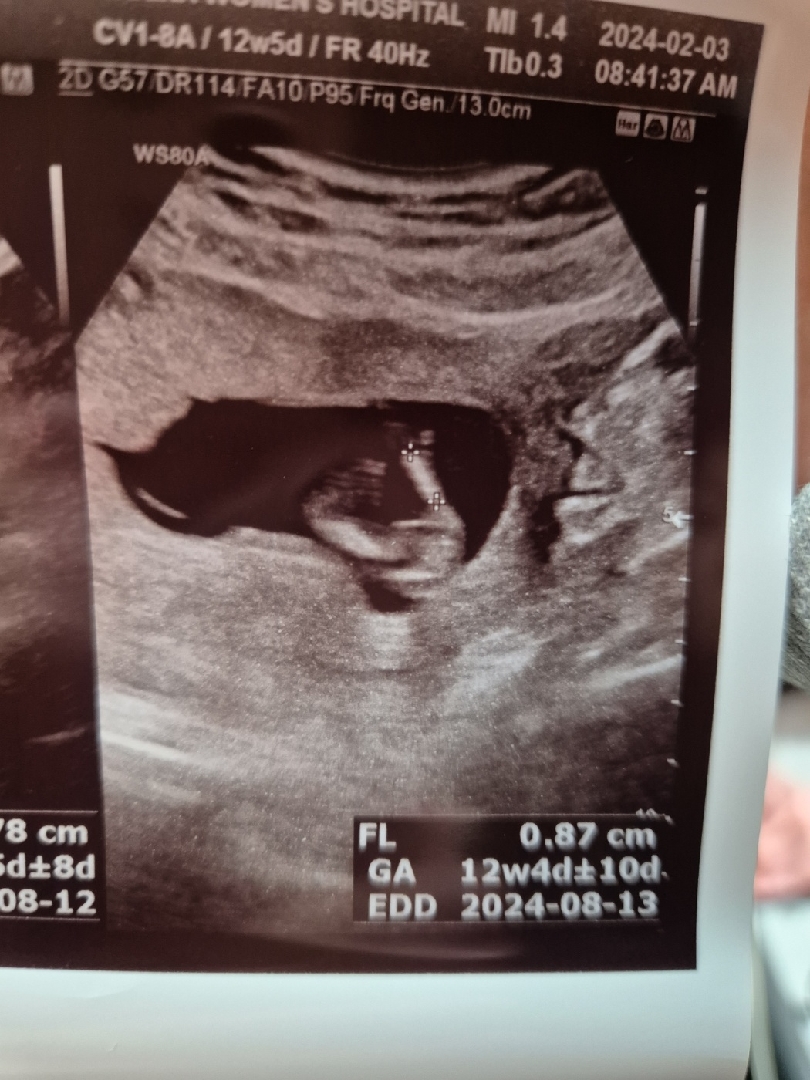

12주5일 성별

입체초음파때 쌤이 자세가 정확하지 않다고 하셨는데 그래도 성별 알수있을까요?